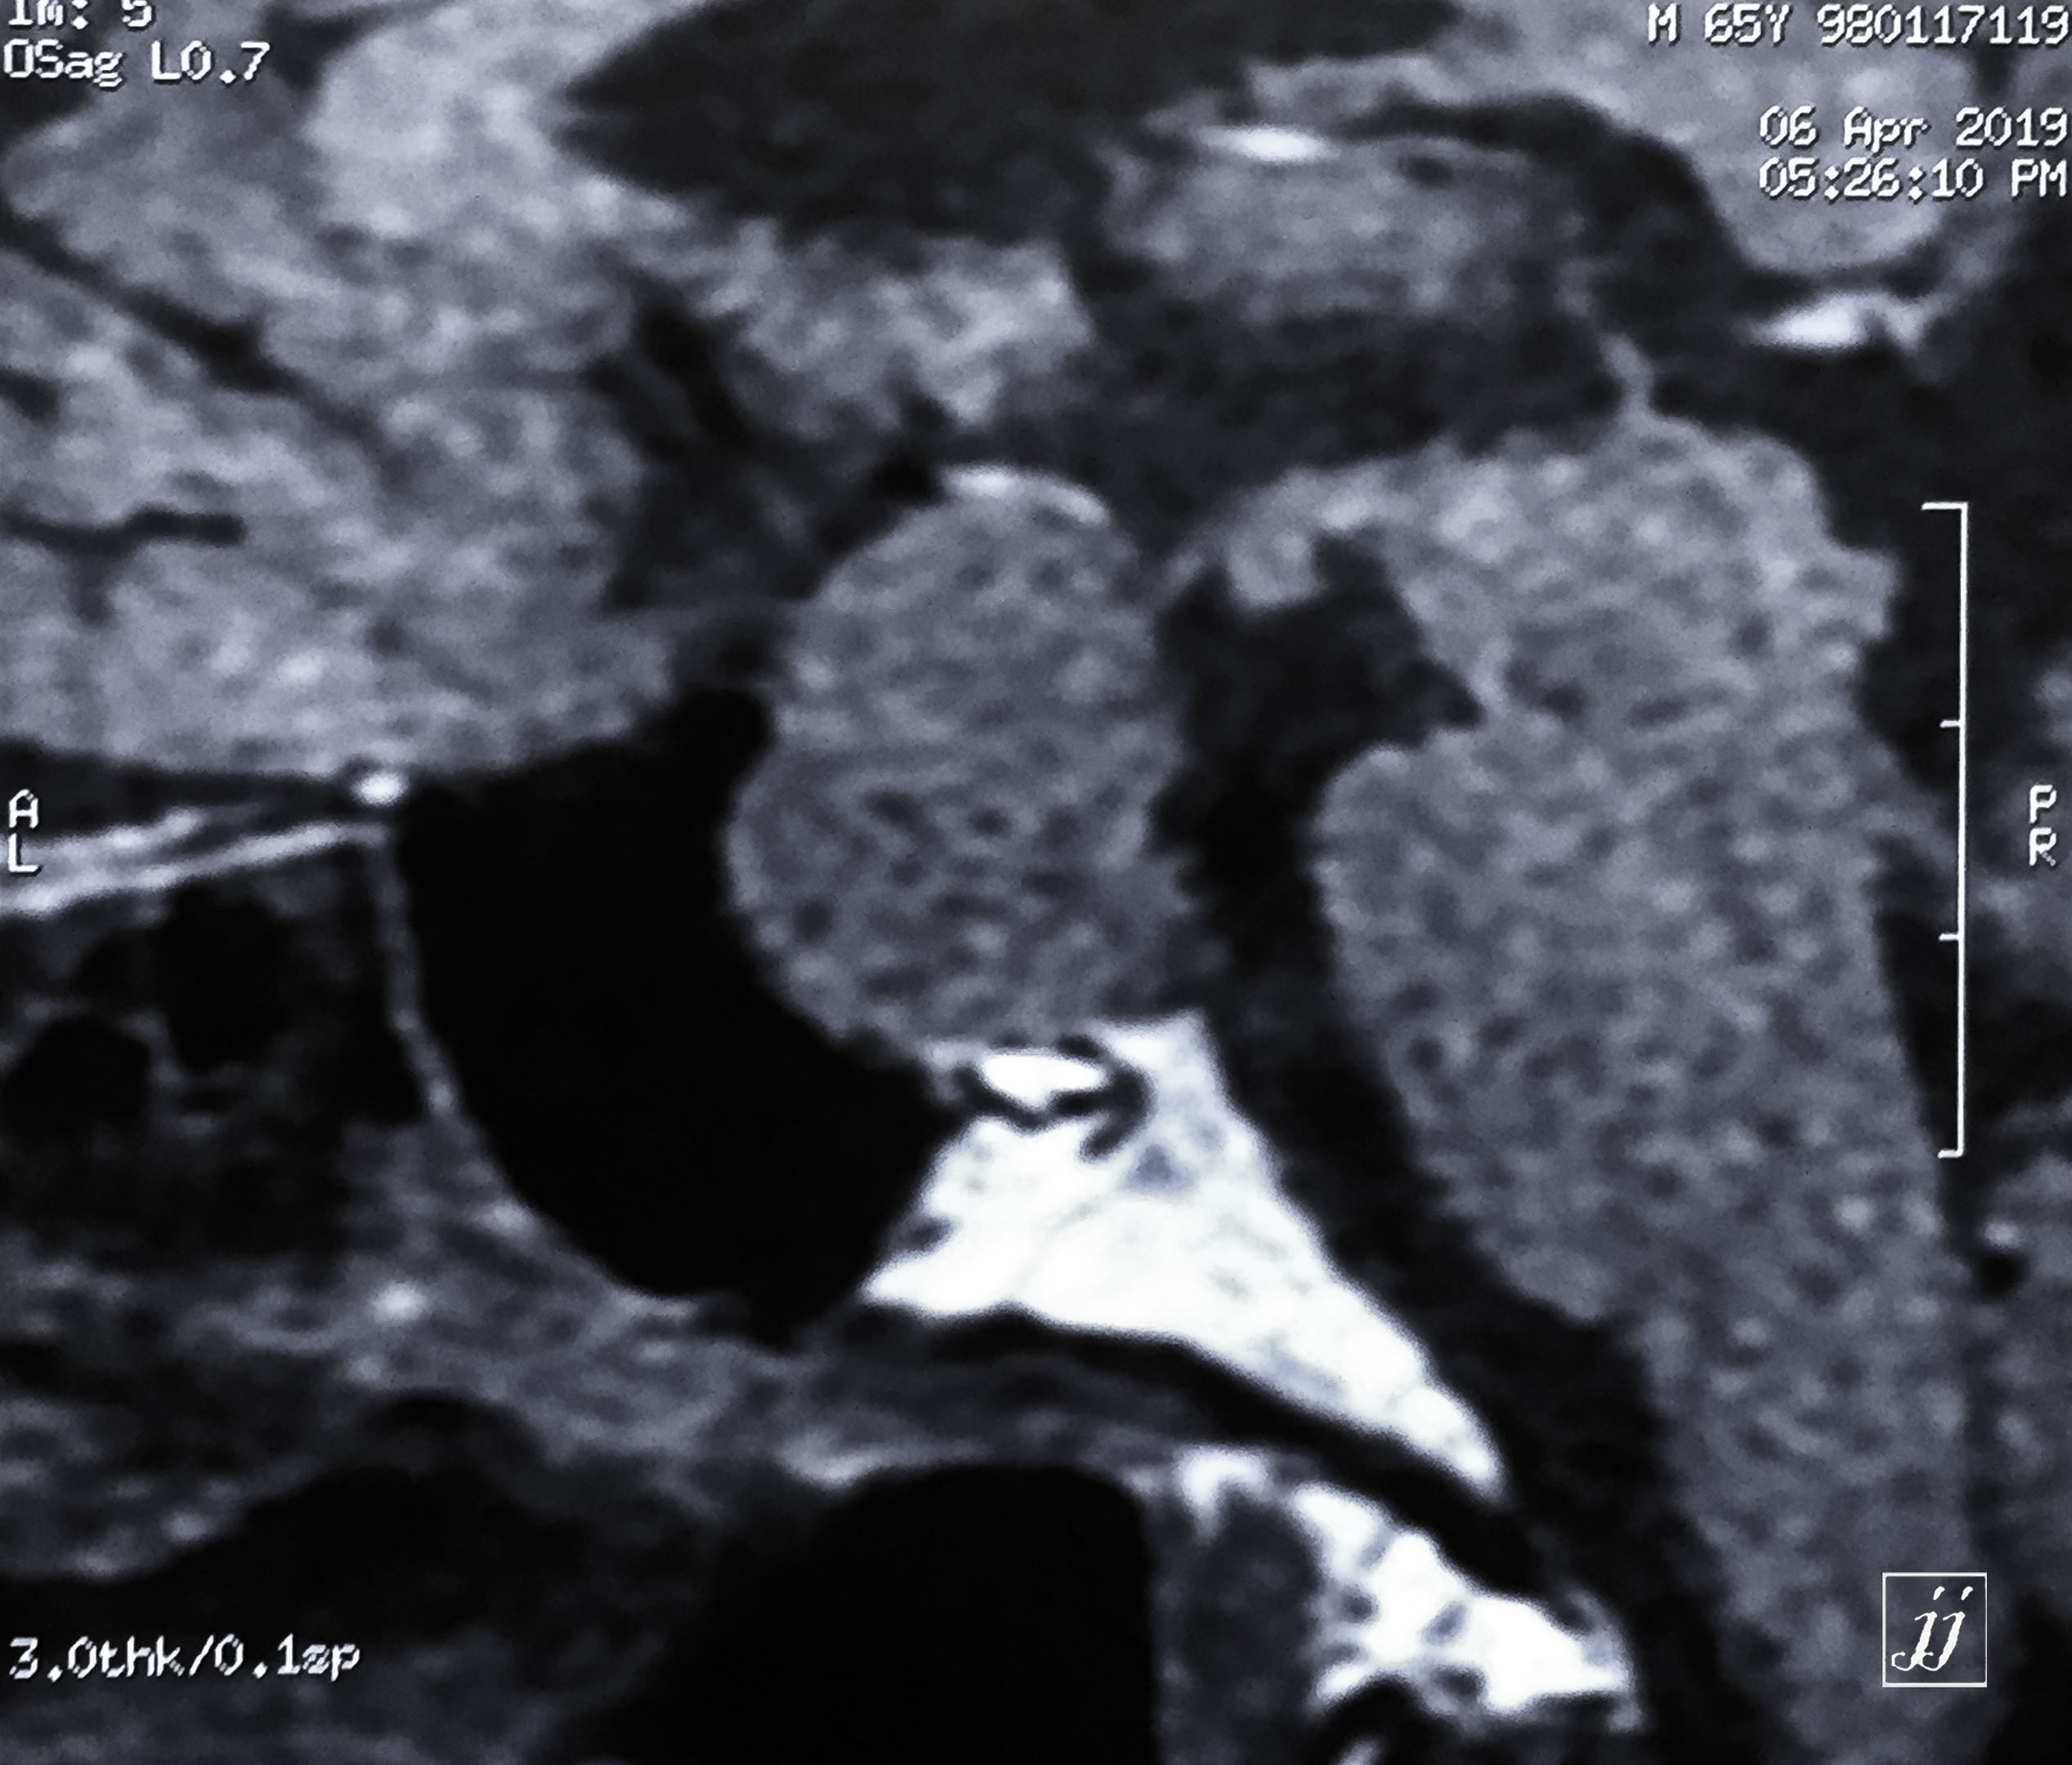

Brain- Hypophysis pituitary macro adenoma (10)